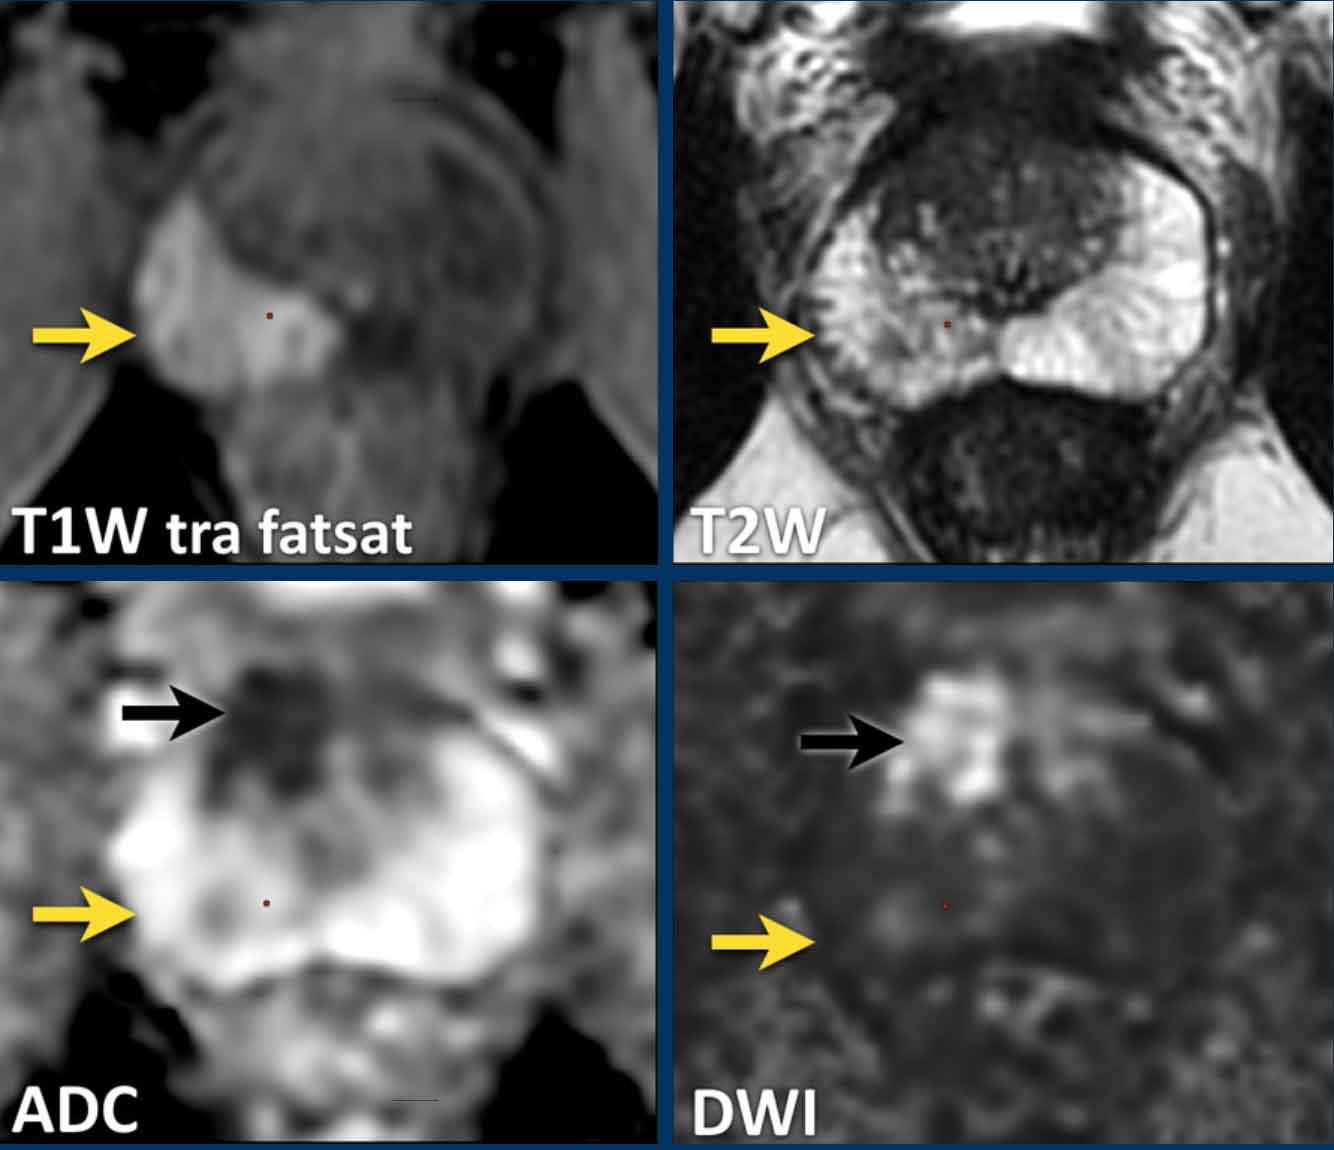

Hãy quan sát hình ảnh trước và mô tả những gì bạn thấy.

Một tổn thương kích thước 16 mm (không hiển thị phép đo) được phát hiện, nằm ở phía sau vùng ngoại vi của phần giữa tuyến tiền liệt bên phải.

Tổn thương này được xếp vào phân loại PI-RADS 5, dựa trên giảm tín hiệu rõ rệt trên ADC và tăng tín hiệu rõ rệt trên DWI (điểm 5 – chuỗi xung chính), đối chiếu với giảm tín hiệu rõ rệt trên chuỗi xung T2W (điểm 5).

Điểm Gleason là 3+4, cho thấy nguy cơ trung bình của một ung thư có tính xâm lấn cao.

Tổn thương không tiếp xúc với vỏ bao giả và không có dấu hiệu xâm lấn ra ngoài tuyến tiền liệt.

Hãy quan sát hình ảnh trước rồi tiếp tục đọc.

Các phát hiện bao gồm:

- Một tổn thương kích thước 17 mm (không hiển thị phép đo) nằm ở vùng ngoại vi, phía sau bên trái của phần giữa tuyến tiền liệt.

- Giảm tín hiệu rõ rệt trên ADC và tăng tín hiệu rõ rệt trên DWI.

- Tương ứng với vùng giảm tín hiệu trên chuỗi xung T2W.

- Trên chuỗi xung T2W, tổn thương tiếp xúc diện rộng với vỏ bao tuyến tiền liệt.

Tổn thương này được xếp vào phân loại PI-RADS 5 với nghi ngờ xâm lấn ra ngoài tuyến tiền liệt.

Điểm Gleason là 4+3.

Tổn thương nghi ngờ này có hạn chế khuếch tán đáng kể.

Giá trị ADC đo được là 440 mm²/s.

Giá trị ADC thấp cho thấy nguy cơ ác tính cao hơn.

Giá trị ADC thực tế có tương quan nghịch với khả năng ác tính có ý nghĩa lâm sàng.

Các giá trị trên 900 mm²/s được coi là có khả năng lành tính và dưới 750 mm²/s có khả năng ác tính.

Tuy nhiên, kết quả định lượng có thể khác nhau đáng kể giữa các máy chụp và các giao thức chụp.